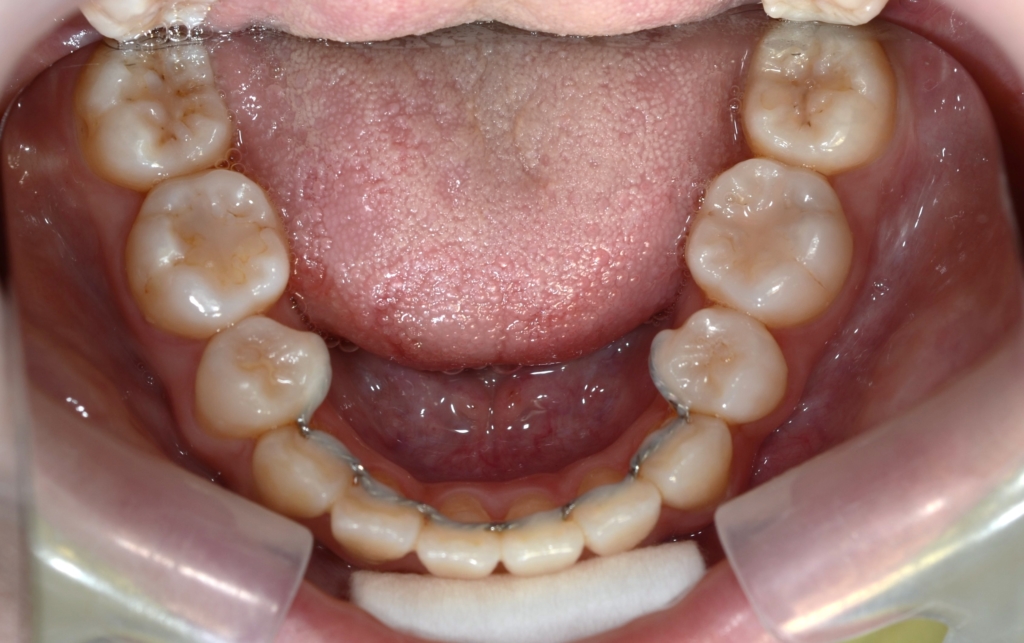

ついでに、歯並びの比較です

上段が矯正治療前、下段が矯正治療後